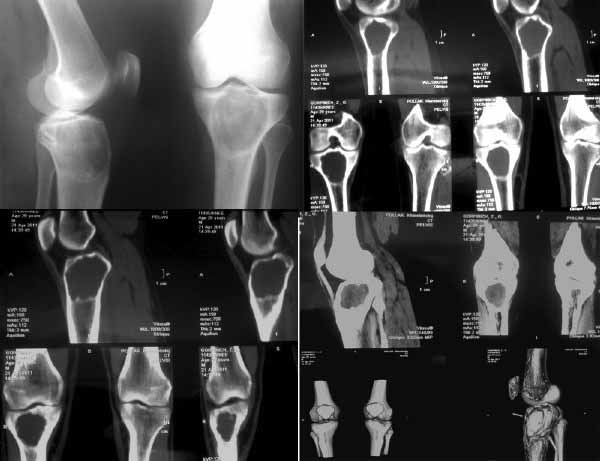

Здравствуйте, уважаемые коллеги! Хотелось бы услышать ваше мнение о тактике лечения. К нам обратилась пациентка 29 лет. В конце марта после нагрузки появился дискомфорт в коленном суставе. К коллегам обратилась в апреле, при рентгенографии обнаружена солитарная костная киста? (фиброзная дисплазия?) Жалоб не предъявляет. Локальных изменений нет.Функция опоры и ходьбы не нарушена.Рентгенограммы и СКТ прилагаются.

Планируется экскохлеация, костная ауто-аллопластика кортикально-губчатыми гранулами.

Интересует ваше мнение об иммобилизации конечности после данного этапа: внешняя иммобилизация, наружный или погружной фиксатор (есть возможность использования LCP. В таком случае больше подойдёт медиальная/латеральная мыщелковая пластина?) Зарнее благодарен за ваши советы!

Рентгенологически - 90% вероятности гигантоклеточная опухоль большеберцовой кости